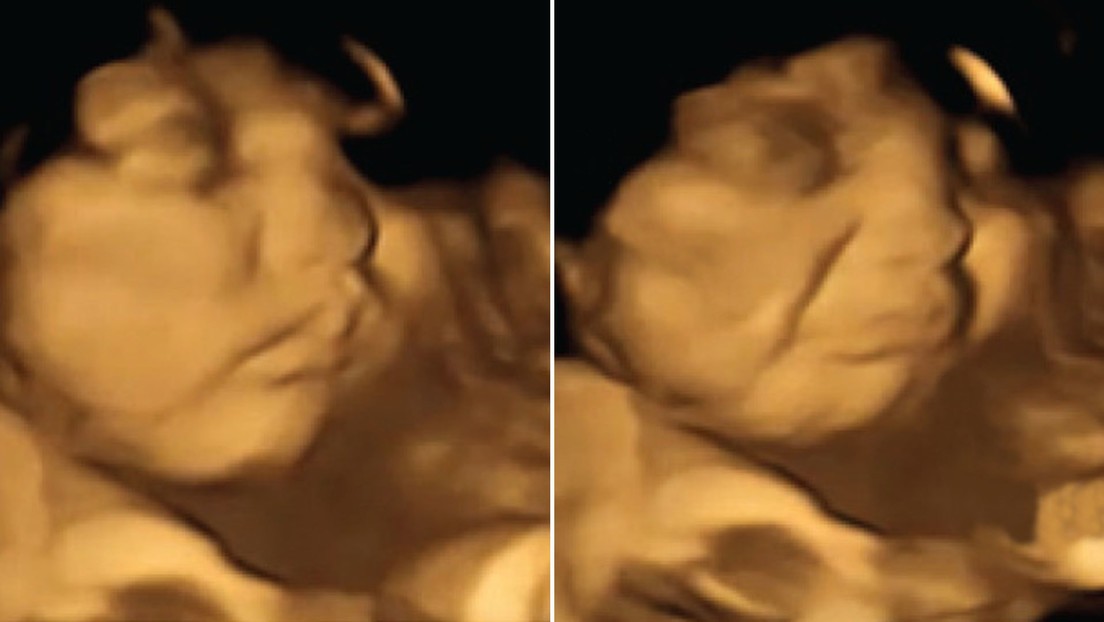

Los científicos tomaron ecografías 4D (imagen del feto en tres dimensiones en tiempo real) de 100 mujeres de 18 a 40 años, con un periodo de gestación de entre 32 y 36 semanas.

Los fetos expuestos al sabor de zanahoria mostraron más respuestas de "cara de risa", mientras que los expuestos al sabor de col rizada mostraron más respuestas de "cara de llanto". La exposición a solo una pequeña cantidad de estos vegetales fue suficiente para estimular una reacción de disfrute o desagrado hacia estos alimentos.